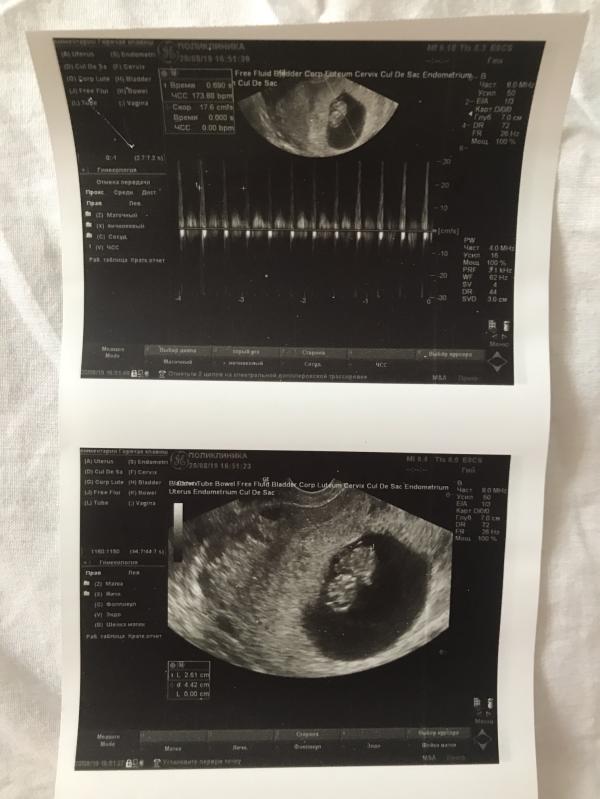

Встала на учёт ✨ сделали узи, крошка хорошо себя чувствует 😍🙏🏻173ударов сердечко❤️в жк дали снимок, что меня удивило, на первую беременность я получила снимок только на 36 неделе и то в роддоме😂и это единственный снимок за всю беременность, а в эту беременность у меня уже 3й снимок пупсика😂❤️10 полных недель сегодня. Уже скоро 1й скрининг (есть страхи) надеюсь, что все будет отлично. Вообще на эту беременность у меня куча переживаний и страхов🤰🙏🏻самое главное здоровье. 28 августа назначен приём, буду сдавать кровь 😭я так и не привыкла ее сдавать всегда становиться плохо. Как вижу эти ампулы ..всё голова кружиться 😩сказали взять с собой что нибудь поесть. Что брали?